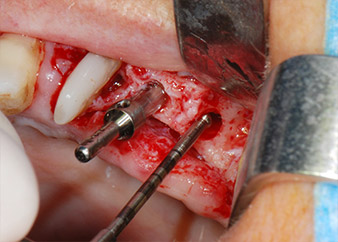

However, we maintained our initial plan to retain both teeth as temporary bridge abutments during the six-months osseointegration period of the implants. At reentry, the situation would have to be reassessed. First, in an attempt to manage the endo-perio problem, the remaining root surface was carefully debrided with piezoelectric equipment (Piezomed, W&H, used with the spatula-shaped insert S1, originally designed for erosion of the lateral sinus wall) (Fig. 4).

periodontium

Fig. 4: To preserve the tooth as a temporary abutment, the periodontium was debrided with piezoelectric equipment …

buccal apex of tooth 24

Fig 5: ... and the buccal apex of tooth 24 was abraded with the same instrument (apicoectomy).